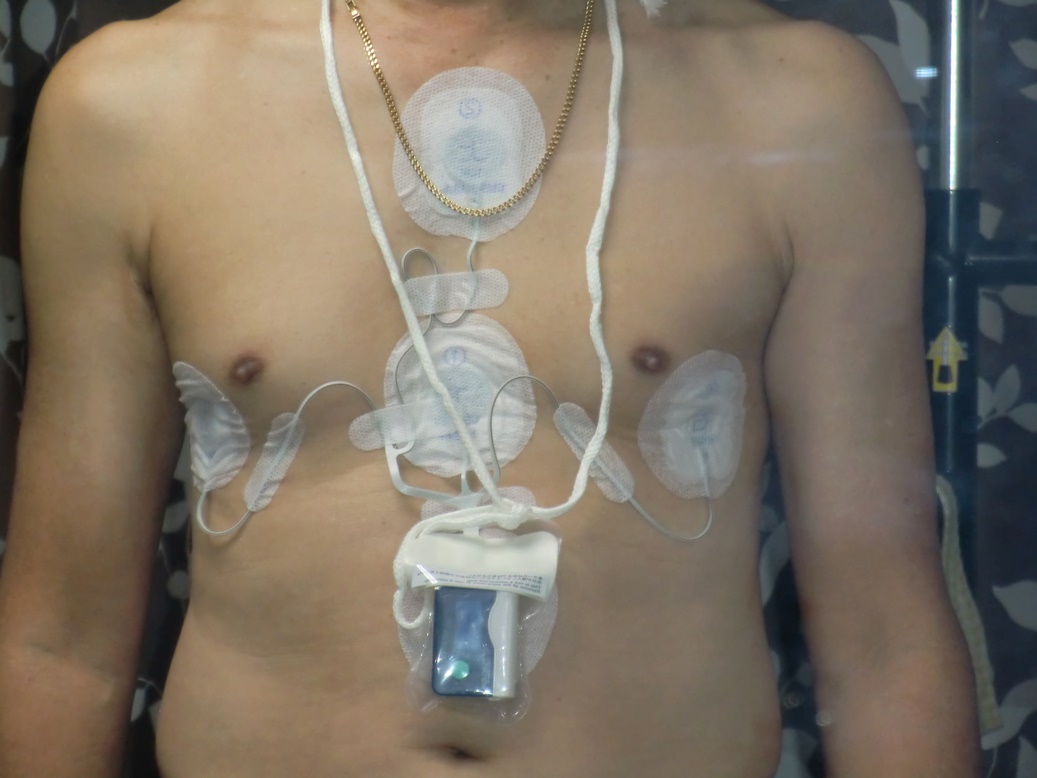

今日は心臓の定期検査の一部として、24時間心電図計を取り付けに行きました。

今の掛かり付けの医師からの紹介で、最初に診てもらっていた病院に行った訳ですが、今日はこ

の心電図を取り付けるだけと聞いていたので、すぐに終わるものと思っていたところ、20日に受

ける予定の心エコーと、腹部エコーまでしますというのでこの病院の連絡の悪さに爆発してしま

いました。

結局病院側の言い分をねじ伏せて、心電図の取り付けだけになりましたが、今度はその前にふつ

うの心電図をとると言いだしまたここで一悶着です、ここでも自分の言い分を通し機械の取り付

けだけにしてもらいました。

最後に診察費を払って帰るのですが、これを取り付けるだけで5.350円でした思わず内訳を聞いて

帰りましたが、家に帰ってからもイライラが治まりませんでした。